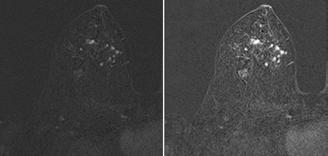

În cadrul Centrului de Imagistică al UMF Craiova, folosim deja soluții bazate pe IA în activitatea zilnică, ceea ce demonstrează aplicabilitatea practică a acestor tehnologii. Spre exemplu, în portofoliul experienței noastre se numără programe de IA capabile să analizeze atât achiziții CT, cât și IRM. Astfel, dispunem de un software de IA specializat în

analiza CT-ului toracic, care detectează automat nodulii pulmonari și îi evidențiază vizual direct în cadrul investigației. În plus, algoritmul generează un raport detaliat ce include localizarea exactă a fiecărui nodul, dimensiunile liniare (diametrele), volumul, precum și un scor de suspiciune oncologică. <figura 1> De asemenea, software-ul furnizează recomandări standardizate de follow-up, conform ghidurilor actuale, facilitând astfel o abordare mai rapidă, precisă și uniformă a cazurilor. Prin aceste funcționalități, AI-ul sprijină radiologul în depistarea precoce a leziunilor, reducând riscul de omisiuni și contribuind la o stratificare mai adecvată a riscului pacientului.